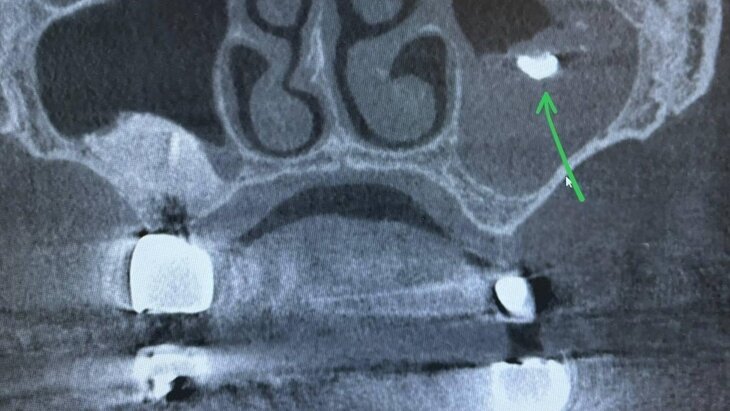

Фото: министерство здравоохранения Московской области

По итогам компьютерной томографии медики обнаружили фрагмент пломбировочного материала в верхнечелюстной пазухе женщины. Инородное тело стало причиной возникновения мицетомы – скопления грибковых масс внутри пазухи.